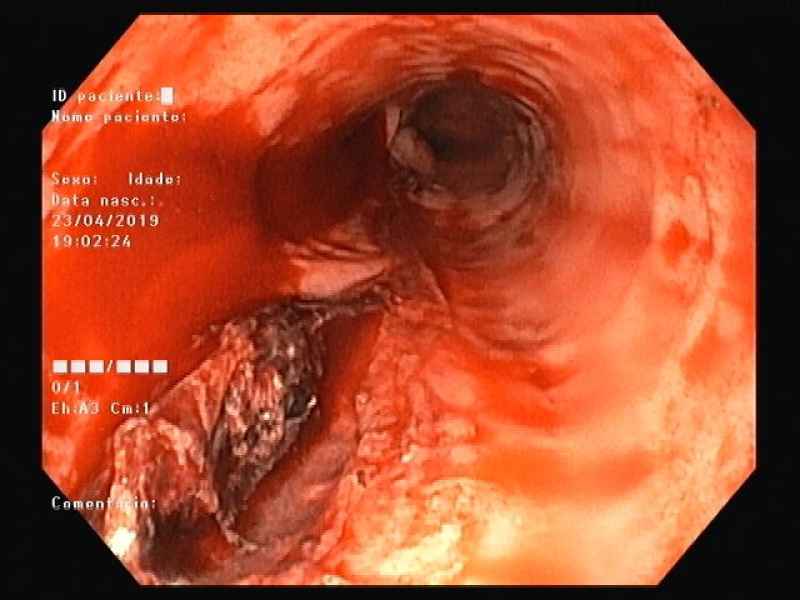

A rare acute gastritis in a teenager

Fotografia